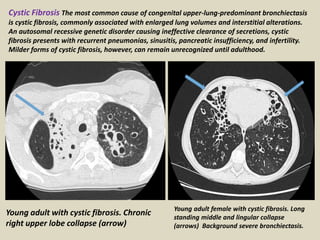

Young adult with cystic fibrosis. Chronic

right upper lobe collapse (arrow)

Young adult female with cystic fibrosis. Long

standing middle and lingular collapse

(arrows) Background severe bronchiectasis.

Cystic Fibrosis The most common cause of congenital upper-lung-predominant bronchiectasis

is cystic fibrosis, commonly associated with enlarged lung volumes and interstitial alterations.

An autosomal recessive genetic disorder causing ineffective clearance of secretions, cystic

fibrosis presents with recurrent pneumonias, sinusitis, pancreatic insufficiency, and infertility.

Milder forms of cystic fibrosis, however, can remain unrecognized until adulthood.